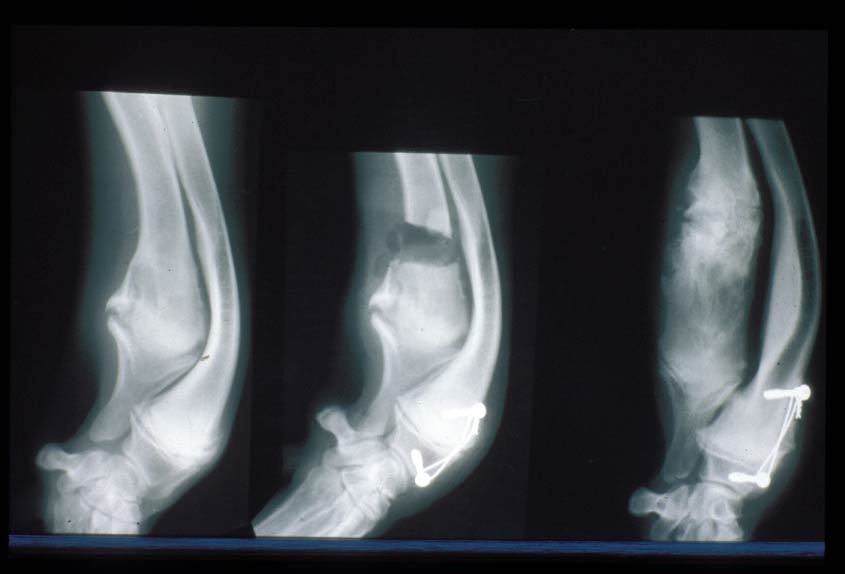

Premature closure of antebrachial growth plates

The most common site for growth deformities is the antebrachium. This is because the radius and ulna must grow at the same rate. 85% of the growth of the ulna comes from the distal growth plate and so it is not surprising that the most common growth problem is premature closure of the distal ulnar growth plate. This causes the ulna to act as a ‘bow string’ on the radius and the radius can start to bow (“radius curvus”). Treatment of this problem can take various forms often depending on the age of the puppy. Careful evaluation, planning and monitoring is necessary for best outcomes. If the problem is caught early, sometimes it is possible to influence growth to reduce the deformity. In other cases, it may be necessary to perform corrective surgery to acutely correct the deformity, and in other cases a gradual correction may be performed using external frames and pins.

Problems with the radial growth plates can also occur but are less common. The distal radial growth plate accounts for approximately 60% of the growth of the radius and the remaining 30% comes from the proximal growth plate. Loss of growth of the radius can cause ‘short radius syndrome’ which can lead to subluxation of the elbow joint. Asymmetrical disease of the distal radial growth plate can cause deformity of the limb (e.g. carpal varus).

The pictures here are of a Flat-Coat Retriever who had growth deformities in both legs.